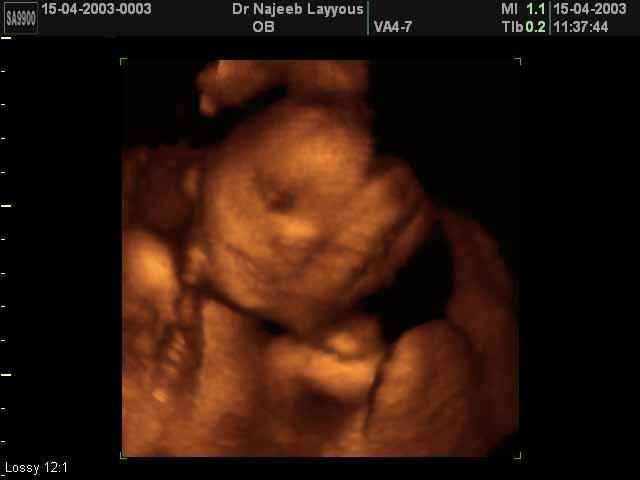

3D second trimestre échographie Photos de numérisation - deuxième partie de la grossesse | Dr N Layyous

3D second trimestre échographie Photos de numérisation - deuxième partie de la grossesse